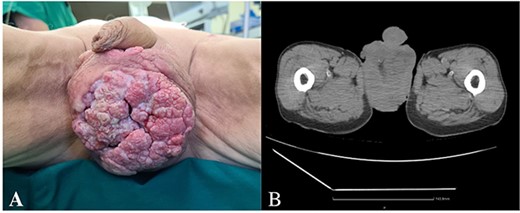

A 62-year-old male with no comorbidities was admitted to the urological oncology department with an 8 cm ulcerating painless tumor in the scrotum (Fig. 1A). He has been observing the formation for two years but has not sought medical help. β-Human Chorionic Gonadotropin concentration was slightly elevated (2.31 mIU/mL). Other laboratory tests were within normal limits.

(A) Ulcerating painless tumor in the scrotum, (B) heterogenous tumor mass in the projection of scrotum (CT).

A whole-body computed tomography (CT) scan showed a heterogenous tumor mass in the scrotum, involving the testicles, surrounded by free fluid (Fig. 1b). Bilaterally enlarged inguinal lymph nodes (l/n), but no metastases in bones or visceral organs were observed.